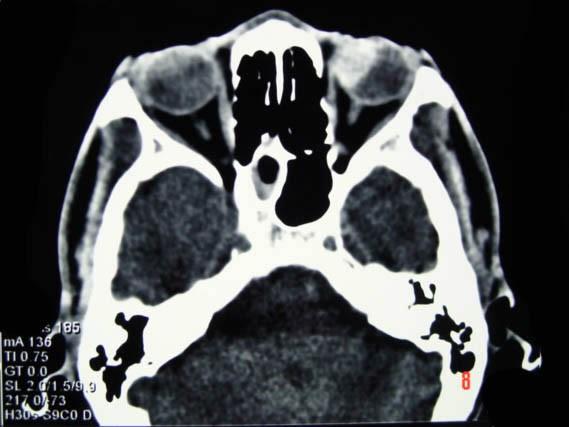

问题 男,37岁,近半年来视力下降明显,近一个月失明,CT如图所示,最可能的诊断为 ( )

选项 A、色素膜神经瘤伴视网膜脱离 B、黑色素细胞瘤伴视网膜脱离 C、色素膜血管瘤伴视网膜脱离 D、色素膜转移瘤伴视网膜脱离 E、色素膜黑色素瘤伴视网膜脱离

答案 E